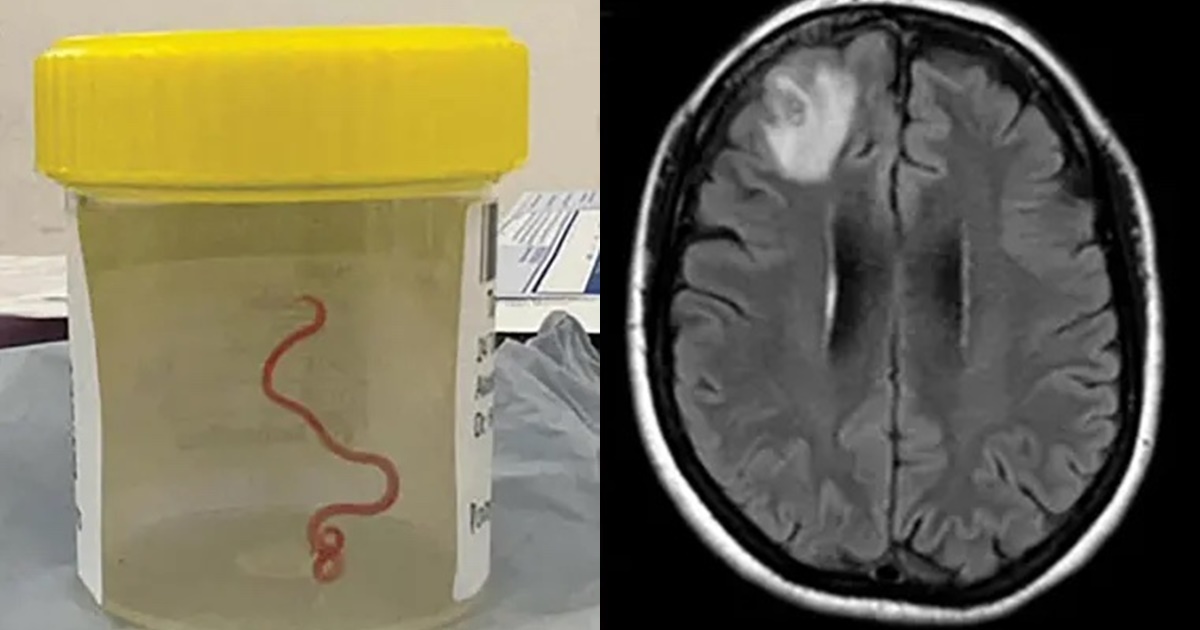

Đến tháng 1/2022, người phụ nữ bắt đầu mắc chứng hay quên và dấu hiệu trầm cảm ngày càng trầm trọng. Những triệu chứng này khiến các bác sỹ phải kiểm tra não của bà. Họ nhận thấy bà có một tổn thương trong não và chỉ định phẫu thuật. Trong ca mổ, các bác sỹ rất sốc khi nhìn thấy một con giun ký sinh trong não và họ càng choáng váng hơn khi nó ngọ nguậy.

Sau khi phân tích, họ xác định đây là một con giun đũa có tên khoa học Ophidascaris robertsi. Đội ngũ y bác sĩ của Bệnh viện Canberra cho rằng đây là trường hợp đầu tiên trên thế giới phát hiện giun đũa trong não người.

Giun đũa Ophidascaris robertsi – thường ký sinh trong vật chủ trăn thảm – đã được lấy ra khỏi não bệnh nhân sau ca phẫu thuật trong trạng thái còn ngoe nguẩy. Các bác sĩ nghi ngờ ấu trùng của loài giun này đã lây nhiễm sang các cơ quan khác trong cơ thể người phụ nữ, bao gồm cả phổi và gan.